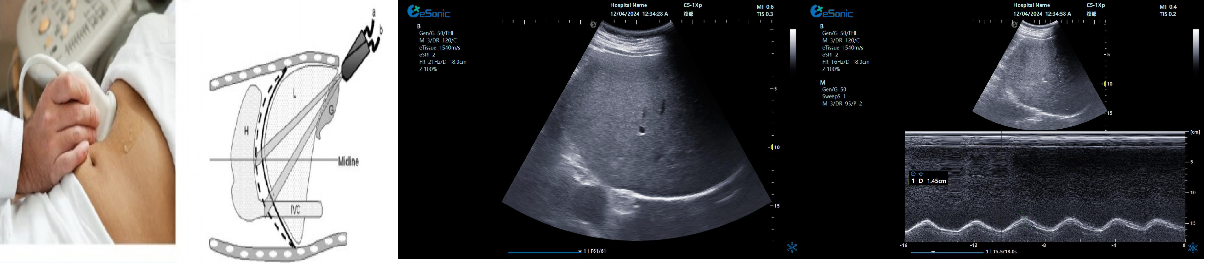

重症心脏超声- FATE方案:

是重症病人循环管理推荐的目标导向超声评估评估方案之一,在此基础上扩展快速的下腔静脉超声检查,增加和完善容量状态和液体反应性的评估。

胸骨旁左心室长轴切面image.png

扫查方法:探头放在胸骨左缘三到四肋间或距胸骨2-3cm处,探头标记指向患者右肩大约9-10点位置

超声声像图:显示左房、左室、主动脉、右室、室间隔及后壁;同时,此切面可观察二尖瓣及主动脉瓣的形态及运动。

剑突下下腔静脉切面

扫查方法:在剑突下四腔心切面的基础上逆时针调整探头,直至标记指向被检者的头部,轻轻将探头向被检者右边倾斜。

超声声像图:显示右房,下腔静脉及肝静脉,注意观察下腔静脉及肝静脉有无扩张及搏动。